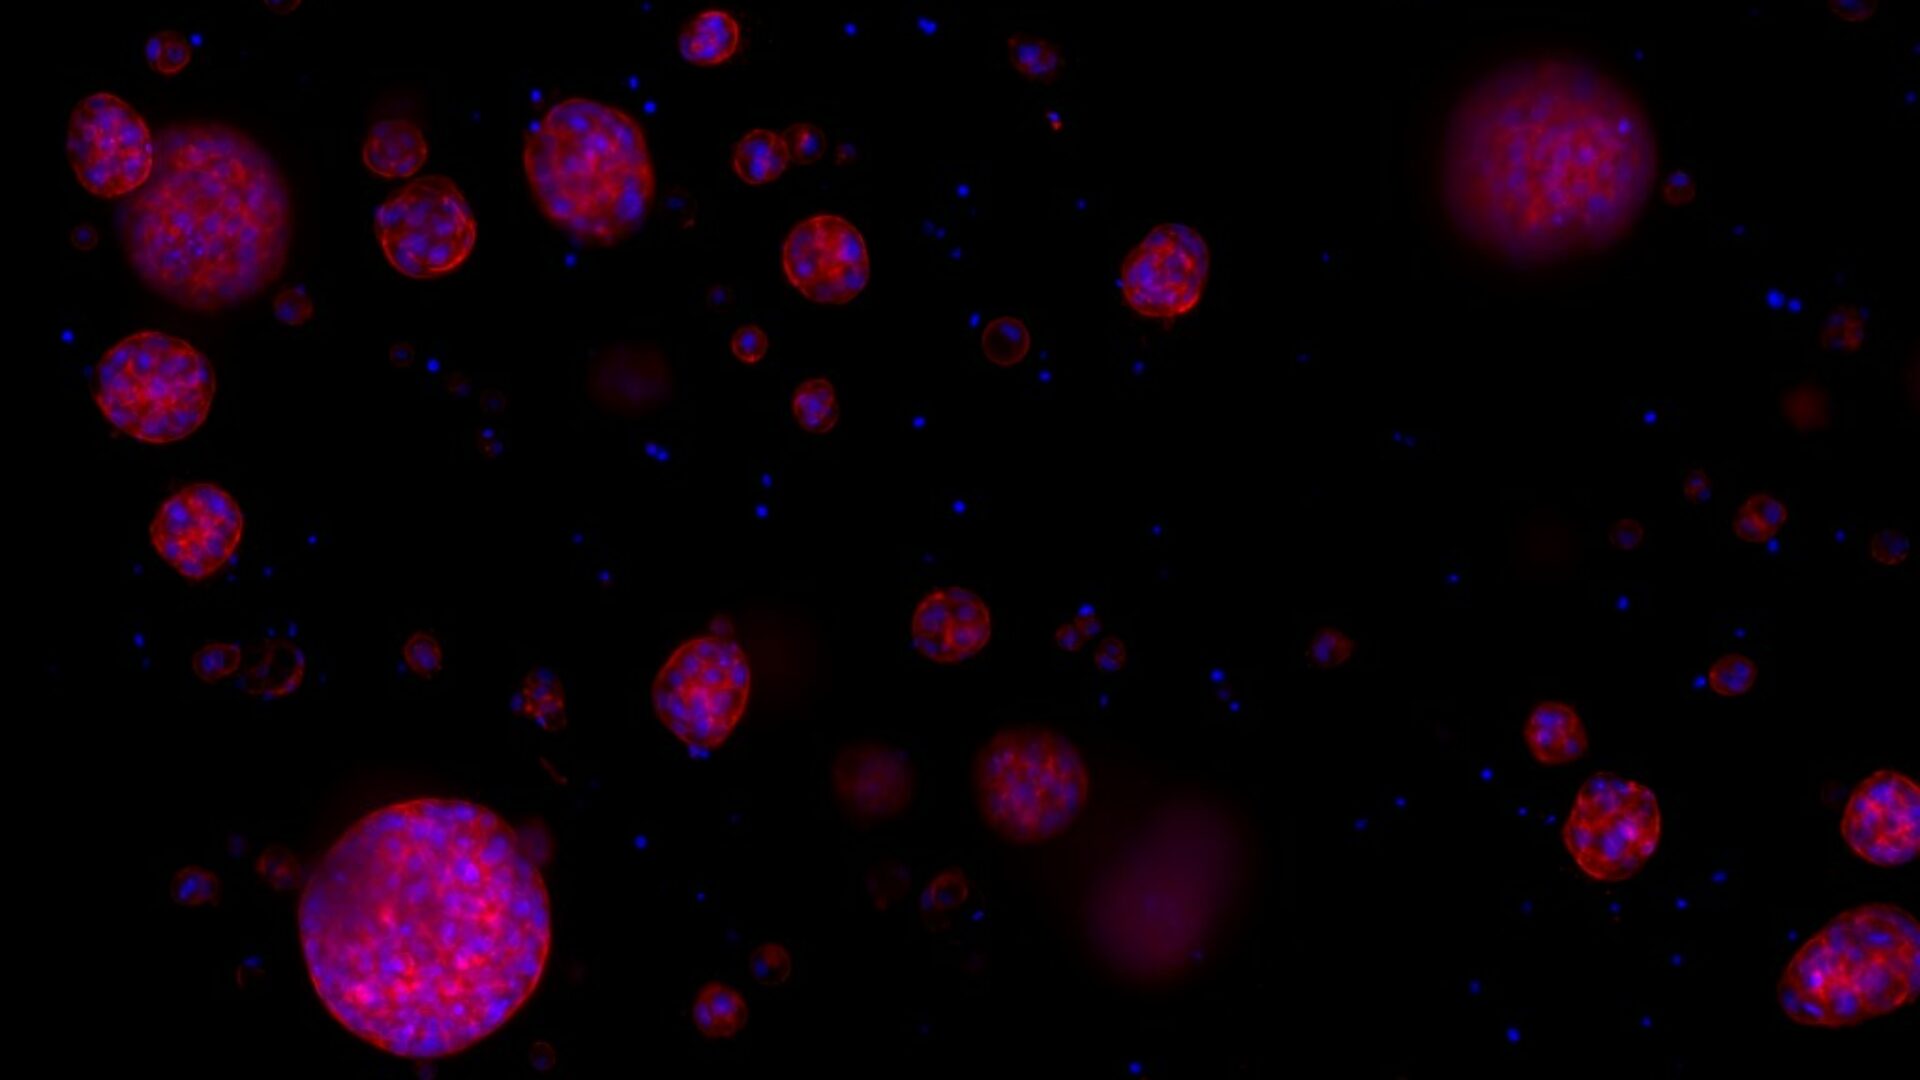

blaas in a dish

Blaastumorweefsel onder de microscoop.